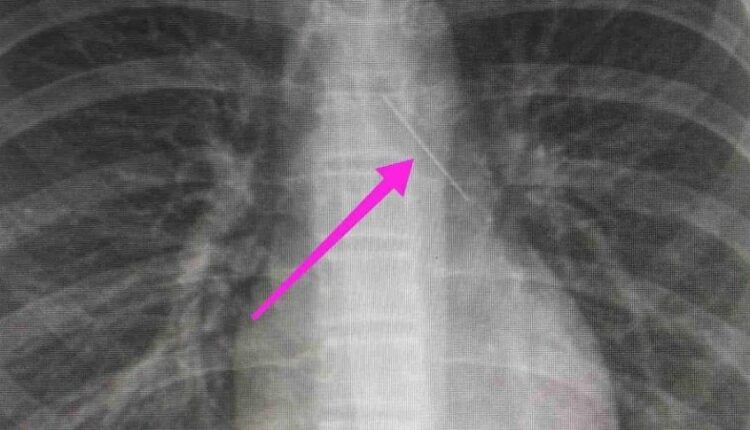

Από την απεικονιστική διερεύνηση που πραγματοποιήθηκε με ακτινογραφία θώρακος αρχικά και ακολούθως με αξονική τομογραφία θώρακος, διαπιστώθηκε η ύπαρξη αιχμηρού μεταλλικού ξένου σώματος στην αναπνευστική οδό (δεξιός κύριος βρόγχος) και όχι στην πεπτική οδό, αναφέρει η ανακοίνωση του νοσοκομείου, στα μέσα κοινωνικής δικτύωσης.

“Χθες 30/1/2022 στις 16:00 στο Τ.Ε.Π. του ΓΝΘ Ιπποκράτειο, προσήλθε ανήλικη συνοδευόμενη από τους γονείς της, μετά από αναφερόμενη κατάποση ξένου σώματος (καρφίτσα). Από την απεικονιστική διερεύνηση που πραγματοποιήθηκε με ακτινογραφία θώρακος αρχικά και ακολούθως με αξονική τομογραφία θώρακος, διαπιστώθηκε η ύπαρξη αιχμηρού μεταλλικού ξένου σώματος στην αναπνευστική οδό (αριστερός κύριος βρόγχος) και όχι στην πεπτική οδό.

Κατά την βρογχοσκόπηση διαπιστώθηκε η μετακίνηση και ενσφήνωση του ξένου σώματος στον δεξιό κύριο βρόγχο. Μετά οπό εργώδεις προσπάθειες ολοκληρώθηκε με επιτυχία η αφαίρεση αυτού. Η ασθενής ανένηψε πλήρως εντός της χειρουργικής αίθουσας. Η ασθενής μεταφέρθηκε για παρακολούθηση και νοσηλεία στη Γ’ Παιδιατρική Κλινική.